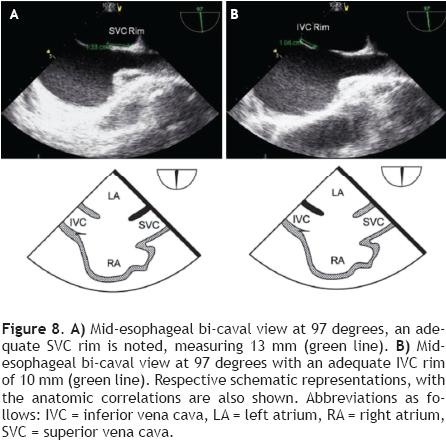

From the mid-esophageal four-chamber view, the multiplane angle is rotated approximately 90° to the 2-chamber view. With slight probe rotation to the right (clockwise rotation of the shaft of the probe), the IVC and the superior vena cava (SVC) are seen. The SVC rim is measured from the superior lip of the ASD to the insertion of the rim into the SVC (Figure 8A). The mid-esophageal bi-caval view provides an excellent view of the inter-atrial septum, allowing interrogation of the septum with CD.

The evaluation of the IVC rim is fundamental (Figure 8B), because PTC would be very challenging in its absence,14 it is, however, usually the most diffcult to visualize and measure, and retrofexion of the probe may help when it is not visible in the standard bi-caval view.15 From the bi-caval view, the TEE probe is advanced into the stomach, retrofexed and slowly pulled back to the lower esophagus. At this point, the IVC rim is measured from the inferior lip of the ASD to the insertion of the rim into the IVC.